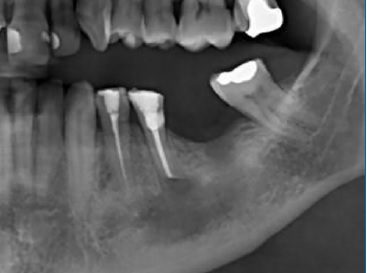

Foi realizado acompanhamento mensal e desgaste gradativo do dispositivo de descompressão, à medida que a lesão sofreu involução de tamanho. Após 4 meses não foi mais possível inserir o dispositivo e foi determinada a remoção do mesmo e acompanhamento (Figura 11). Foi possível observar, radiograficamente, completa remissão da lesão e neoformação óssea após 12 meses (Figura 12) e sinais de maturação óssea após 24 meses (Figura 13). As funções do nervo alveolar inferior foram preservadas. Não houve necessidade de um segundo procedimento cirúrgico e o paciente permanece em acompanhamento radiográfico, sem sinais de recidiva. Além disso, foi encaminhado ao serviço de prótese para avaliação e tratamento protético do dente 35.

Figura 11 Aspeto radiográfico 4 meses após cirurgia paraendodôntica e instalação do dispositivo de descompressão.